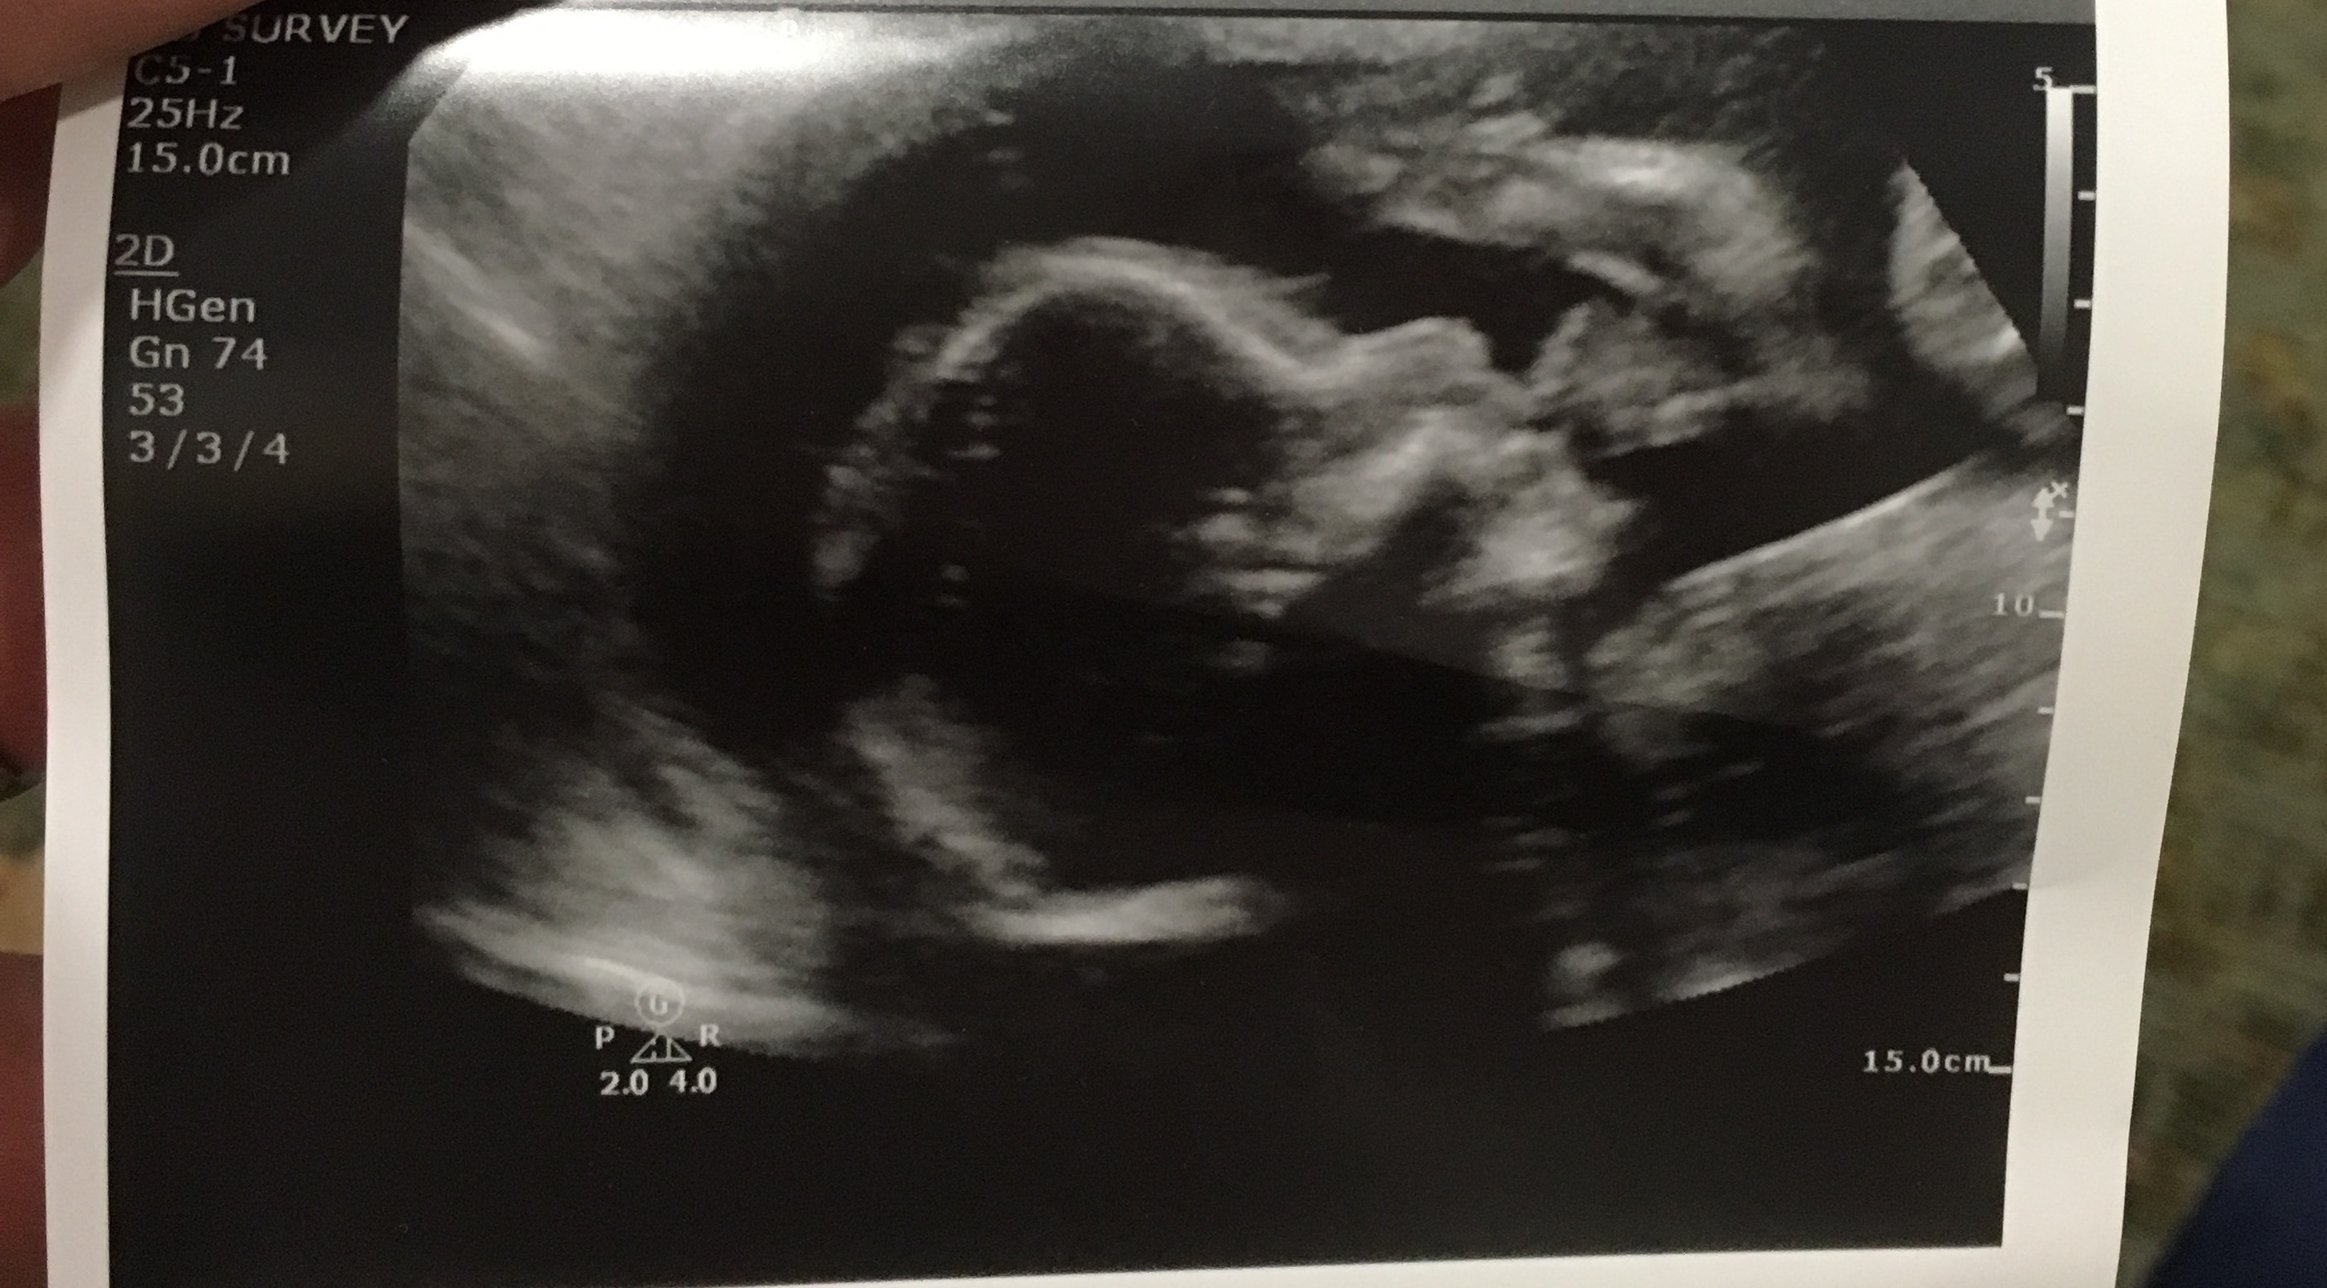

Anatomy scan went well! Hai baby girl!

ETA- after the dr came in to go over the US, everything overall looks good but I do have partial placenta previa, so I'll just have another follow up US around 28wks

• 25wk MFM appt results: HR 154, weighs 1lb 11oz. Looking good :smile: